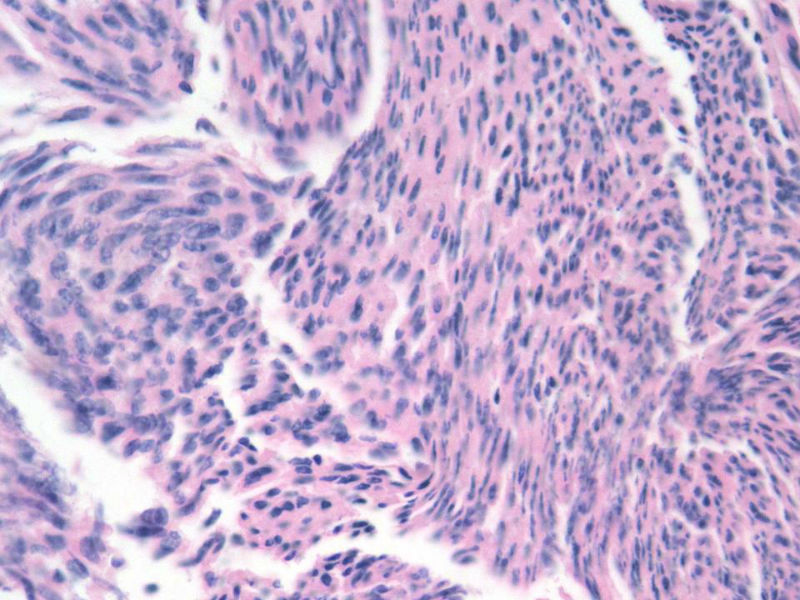

女,64岁,头晕半月,CT检查颅内左颞叶占位,侵犯颅骨和颞肌,手术切除肿物。肉眼,灰白色结节状肿物,3X3X2厘米,边界不清,切面灰黄色,质软。

特别提示:手术前曾做过介入肿瘤栓塞。镜下核分裂15/HP。脑左颞部占位图1

恶性脑膜瘤,有肌肉和骨的侵犯。

梭形细胞与上皮样漩涡状结构,富于细胞,见个别沙砾体,并见肿瘤性坏死。颅骨及其横纹肌等软组织内见肿瘤呈侵袭性生长。但细胞异型性不是很大。鉴别:

1)恶性脑膜瘤

2)非典型性脑膜瘤

由于非典型性脑膜瘤也可以发生地图状坏死,甚至侵袭性生长。需要计数核分裂数/10HPF,以资鉴别诊断。